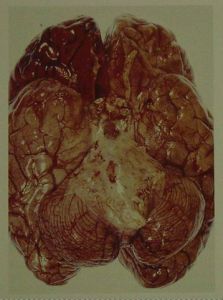

當疑顱內有局限性膿腫,硬腦膜下積液、腦積水可作腦CT檢查。